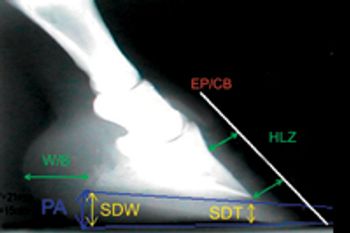

Solving the mathematical needs of a Grade IV laminitic foot.

How to meet the mathematical needs of the higher grades of laminitis.

The mathematical needs of lower grades of laminitis.